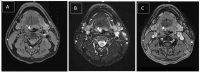

Vascular anomalies encompass a range of conditions affecting blood vessel development, categorized as tumors or malformations. Hemangiomas, the most common vascular tumors, involve abnormal endothelial cell proliferation, particularly in hemangiomas, which are prevalent benign tumors arising from mesenchymal tissue in the head and neck. They manifest as capillary, cavernous, or mixed types, affecting areas like the tongue and lips. Hemangiomas of the tongue base are notably rare, emphasizing the complexity of diagnosis and management due to their uncommon occurrence and potential for complications like bleeding. This report highlights a case of cavernous hemangioma of the tongue base, underscoring diagnostic challenges and management considerations. A Malay man in his late 30s, a nonsmoker and nondrinker, presented with a year-long history of intermittent globus sensation without associated symptoms like odynophagia, dysphagia, intraoral bleeding, or neck swelling. Flexible nasopharyngolaryngoscopy revealed a lobulated bluish mass at the right base of the tongue, prompting a provisional diagnosis of hemangioma. Contrast-enhanced CT suggested an irregular lesion with calcification, leading to MRI confirmation of a well-defined, non-muscle-invasive lesion that favored venolymphatic malformation rather than hemangioma. However, it was confirmed histologically as cavernous hemangioma after excision, where intraoperative findings aligned with initial preoperative clinical assessments.